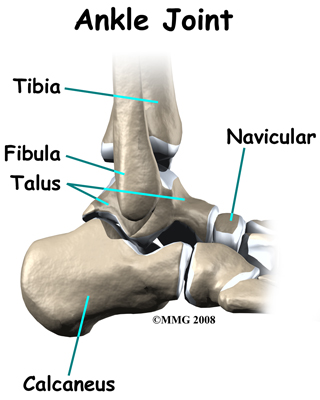

The skeleton of the foot centers around the talus, or ankle bone, that forms the main part of the ankle joint. The two bones of the lower leg, the large tibia and the smaller fibula, come together at the ankle joint around the talus to form a very stable structure.

The foot is able to bend up and down due to the joint formed by the tibia, fibula, and talus.

The foot is able to bend up and down due to the joint formed by the tibia, fibula, and talus.

The two bones that make up the back part of the foot (sometimes referred to as the hindfoot) are the talus and the calcaneus. The calcaneus is the heel bone. The talus is connected to the calcaneus at the subtalar joint. The subtalar joint allows the foot to rock from side to side. People with flatfeet usually have more motion at the subtalar joint than people who do not have flatfeet. This increased flexibility of the subtalar joint results in many compensatory actions of the foot and ankle in order to maintain proper foot alignment during standing and walking.